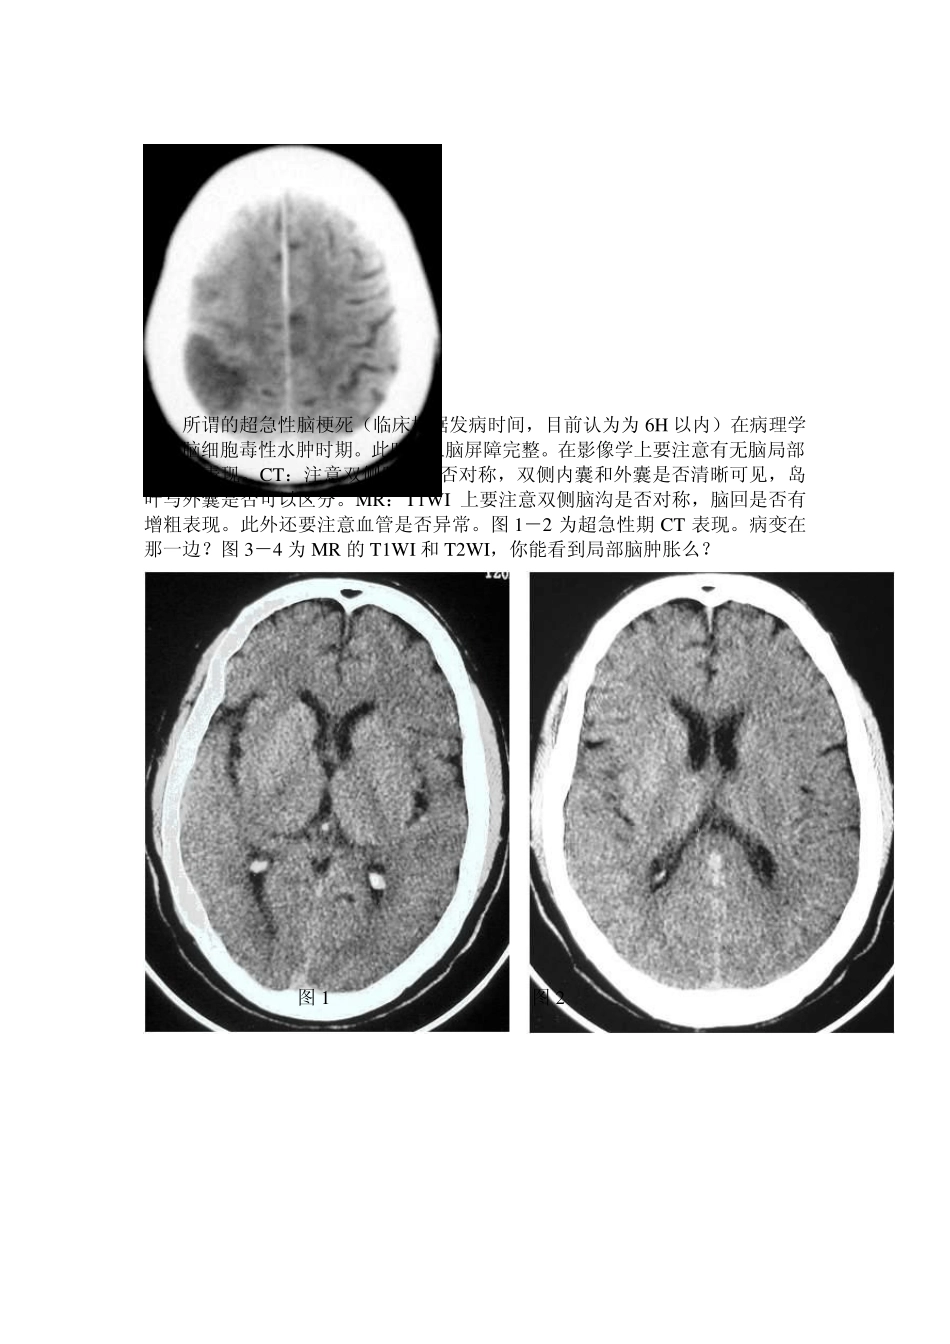

男性,71 岁,左侧肢体无力2 小时,既往健康状况良好。发病后立即查 CT: 从这两张片子看,都没有很明显的病灶,但仔细看可见右侧颞顶叶片状低密度影,脑沟回模糊、皮髓分界不清,1 天后复查 CT: 所谓的超急性脑梗死(临床根据发病时间,目前认为为6H 以内)在病理学上是脑细胞毒性水肿时期。此时,血脑屏障完整。在影像学上要注意有无脑局部肿胀的表现。CT:注意双侧脑沟是否对称,双侧内囊和外囊是否清晰可见,岛叶与外囊是否可以区分。MR:T1W I 上要注意双侧脑沟是否对称,脑回是否有增粗表现。此外还要注意血管是否异常。图 1-2 为超急性期CT 表现。病变在那一边?图 3-4 为MR 的T1W I 和 T2W I,你能看到局部脑肿胀么? 图 1 图 2 图3 图4 图1:左侧外囊与岛叶分界不清。图2:左侧脑沟明显变浅。图3:左侧岛叶盖部的脑回可见增粗;图4:左侧外侧裂内的血管流空影消失。上述表现为超急性期脑梗死的表现。病理基础为细胞毒性水肿。 脑梗塞早期的CT 征象: 1、动脉高密度征(致密动脉征):表现为一段动脉密度增高,CT 值高于正常动脉,而低于动脉粥样硬化斑,其形成机制商不清,主要见于大脑中动脉及其主要分支,其次是椎-基底动脉。 2、岛带征:脑岛灰质、白质界限模糊,呈均一的淡的密度影。 3、豆状核征:豆状核轮廓模糊,密度与脑白质一致或稍低。 4、皮质征:皮质局限性密度减低,与脑白质密度一致。 5、早期低密度改变。 6、占位效应。 以上表现多与脑动脉闭塞后引发的细胞内水肿和血管源性水肿有关,属非特异性表现,其中豆状核征、岛带征、皮质征及早期低密度改变是诊断早期脑梗塞的可*指征,动脉高密度征、占位效应不能单独作为诊断依据。 另外:诊断时需密切结合病史、病征。梗塞灶的CT 表现时间的早晚,除与CT 分辨率和诊断水平有关外,还取决于梗塞灶的大小、部位和缺血程度等。 豆状核征: 左偏瘫1.5 小时,CT 平扫示右侧豆状核密度降低与白质一致 2 天后复查,右侧豆状核区明显低密度影 岛带征: 左偏瘫5 小时,CT 平扫右侧脑岛带区灰质密度降低与白质一致 33 小时后复查,脑岛带区程明显低密度影 皮质征: 偏瘫5 小时,CT示右额颞皮质呈楔形密度减低与白质一致 A 71 岁男性左大脑中动脉梗塞后1.5 小时CT所见。示左岛带消失。(有尾箭头)与正常的右侧岛带对比(三角箭头)。左豆状核似乎正常。 B CT后马上进行左颈动脉造影,示左大脑中动脉M2 段栓子闭塞(有...